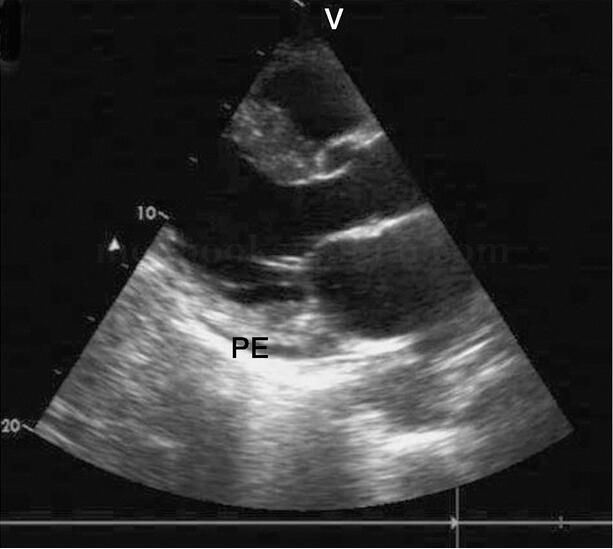

(2)二维超声心动图:积液主要局限于左室后壁区域,也可少量存在于前侧壁、心尖部,左房后方偶可见液性暗区,见图2‐1‐224。在大动脉短轴切面,右室流出道前方可见液性暗区,见图2‐1‐225。在心尖四腔心切面上,右室、左室侧壁、心尖部也可检测到液性暗区,如图2‐1‐226所示,液性暗区位于右房顶部及左心室外侧。剑突下四腔心切面液体位于右室前壁、心尖部和左室后壁。

图2‐1‐225 房间隔缺损患者,大动脉短轴切面显示中量心包积液PE:心包积液